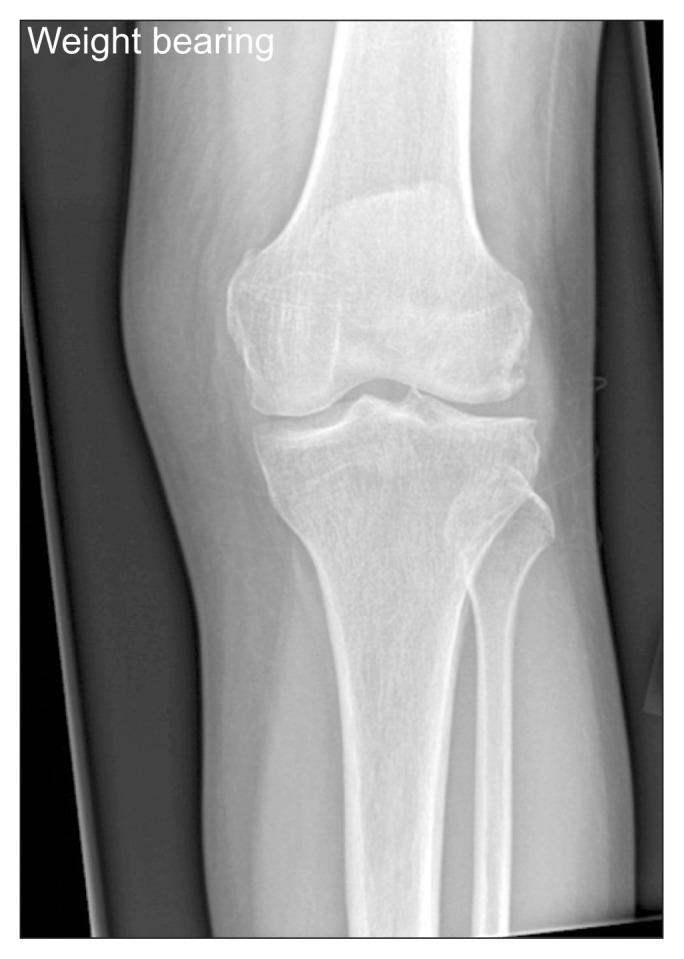

A 64-year-old marathon runner presented to our clinic with a history of worsening pain in her left knee. Following magnetic resonance imaging, the diagnosis of subchondral insufficiency fracture of the knee (SIFK) was made. A course of conservative management via bisphosphonates was initiated. The patient successfully recovered and returned to full athletic function, having recently returned to competitive marathon running. This article aims to present this unusual case of lateral compartment SIFK and summarise the literature on this uncommon condition.

一名64岁的马拉松运动员因左膝疼痛加重前来我院就诊。经磁共振成像检查后,诊断为膝关节软骨下不全骨折(SIFK)。开始了通过双膦酸盐进行的保守治疗疗程。患者成功康复并恢复了全部运动功能,最近已重返马拉松比赛。本文旨在介绍这例罕见的外侧间室SIFK病例,并总结关于这种罕见病症的文献。